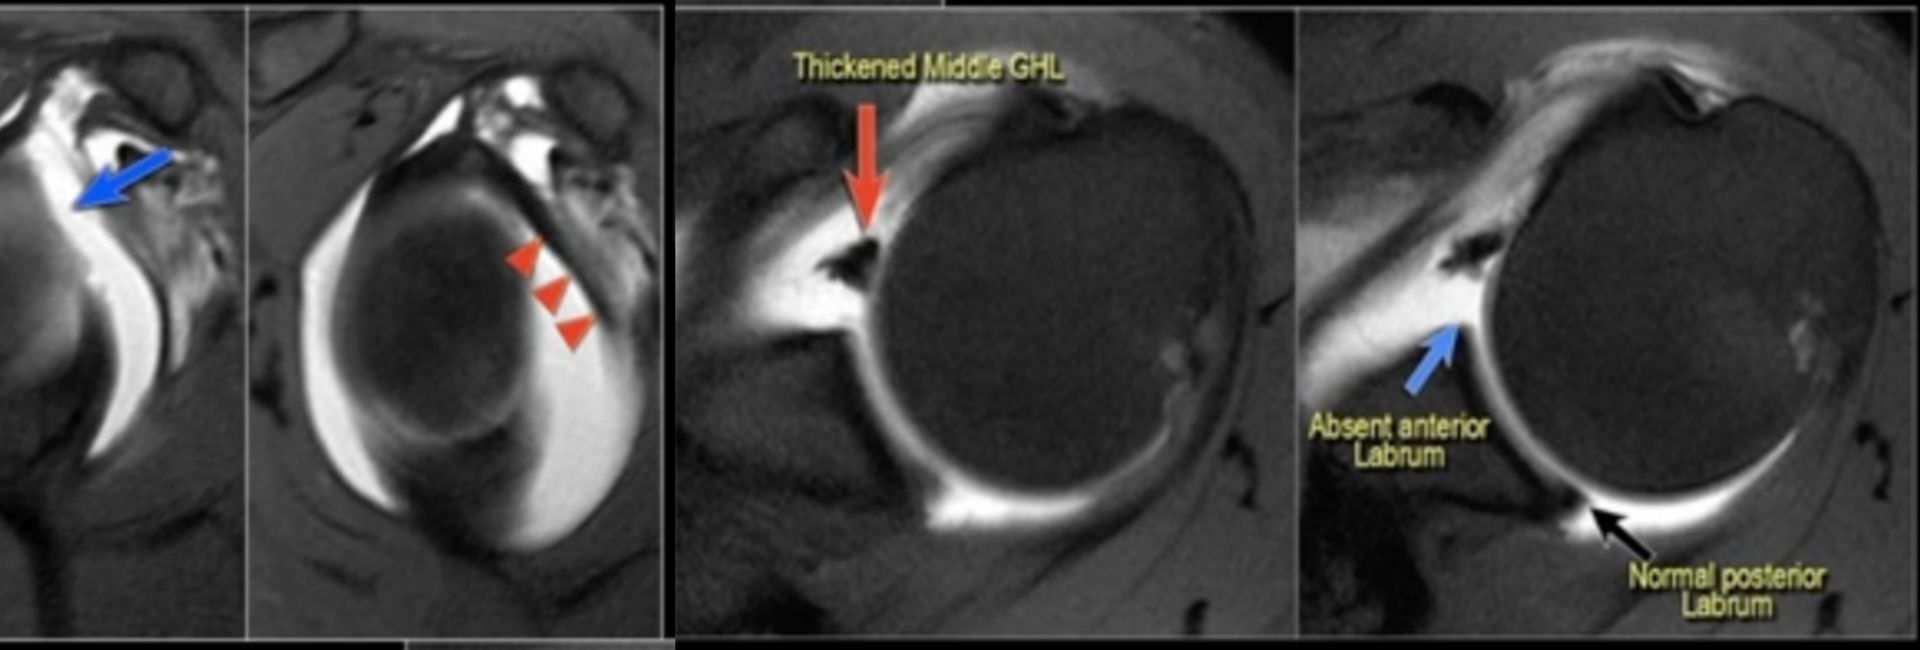

Комплекс буфорда

Комплекс буфорда 110 фото